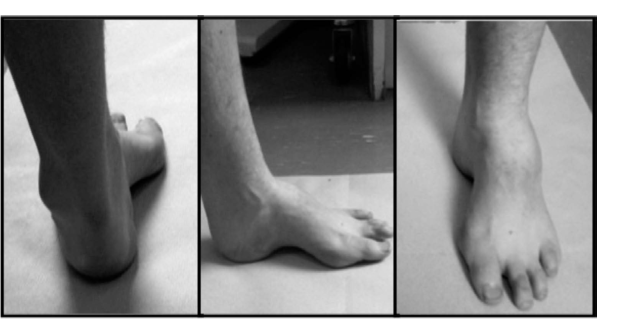

Structured oral examination question 4: Cavus foot EXAMINER : These are pictures of the left foot of a 20- ye…